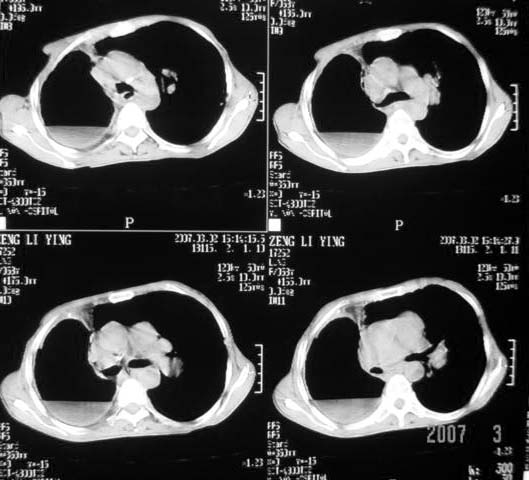

以下是引用dyqct在2007-3-2 22:04:00的发言:[br]考虑:1、右侧毁损肺伴支气管胸膜瘘(多条支气管与胸腔相通、液气胸);[br] 2、左肺浸润型肺结核。[br][br][br][br]